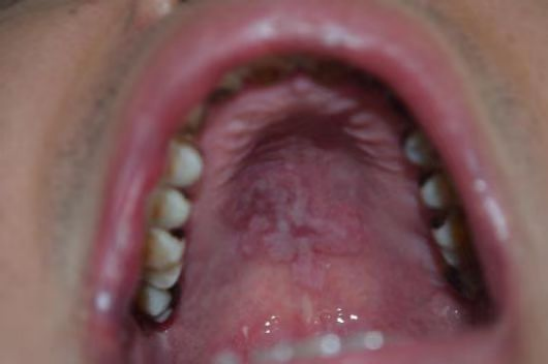

梅毒患者口腔

HIV患者毛状白斑伴真菌感染